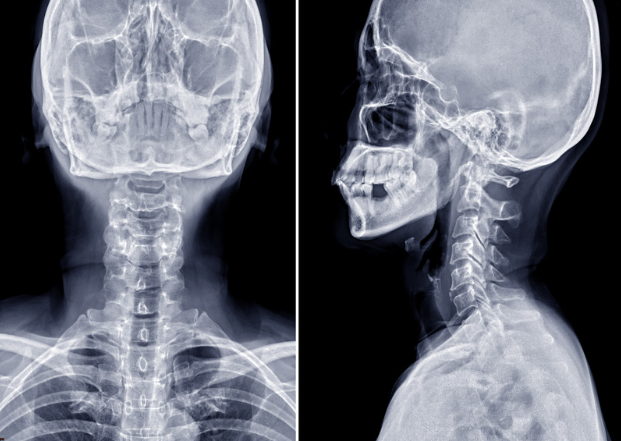

ストレートネック・スマホ首の診断

まずレントゲンを撮像し、正面と側面、顎を引いた状態、顎を上げた状態での頸椎の骨の並びや動揺があるかを評価し診断を行います。首の痛みが悪化しない範囲で撮影しますので、ご安心ください。